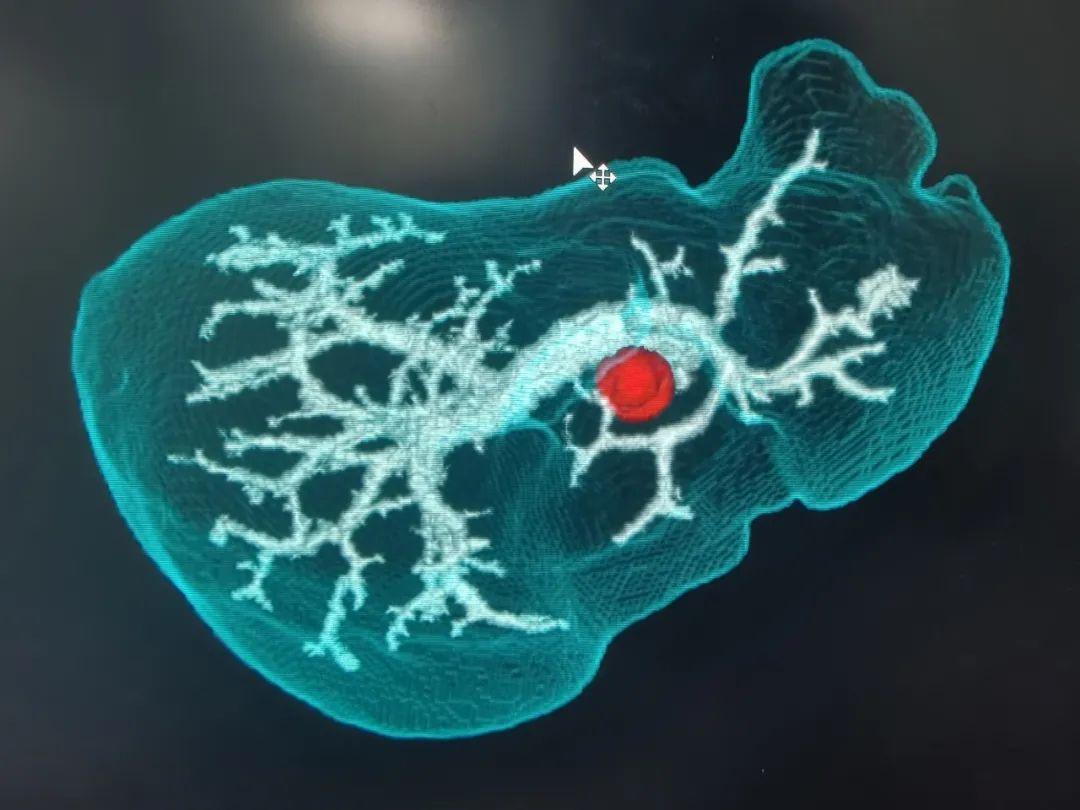

经过详细的体格检查,完善影像和实验室检查后,诊断其为:肝门胆管恶性肿瘤。普外科主任代坤介绍,肝门部胆管癌,就是长在肝门部胆管粘膜上皮的恶性肿瘤,因为位置特殊,起病隐匿,可能与胆管慢性炎症、胆管结石等有关。长期胆管炎会让胆管粘膜反复受损修复,胆管粘膜增生,可能发展成癌;有先天性胆管囊性扩张症、原发性硬化性胆管炎的人群,患癌的几率更高。值得警惕的是,患者早期症状可能不明显,随着肿瘤的生长,胆管被堵住,胆汁排不出去,黄疸会特别突出,出现皮肤、巩膜黄染,患者可能会有右上腹隐痛、胀痛,因为肿瘤影响消化,患者营养吸收不好消耗较大,会有吃不下饭、消瘦、没力气的表现。

基于术前影像,结合肿瘤实际累及程度、解剖变异以及切离极限点,外科团队邀请多科室开展MDT讨论,规划个体化精准手术方案。充分术前准备后,为其行“肝门部胆管癌根治术”。主刀手沉着冷静,仔细探查,精准分离,清扫组织,以雷霆之势完整切除病灶。“清点器械纱布,确认无误,关腹。”手术顺利,经过术后严格管理和精心护理,宗师傅很快康复出院,对东方医院集团广济医院普外科团队精湛的技术赞不绝口。

“根治术手术切除被认为是肝门部胆管癌最佳治疗方式。”代坤主任解释道:肝门部胆管癌根治术被称为“肝胆外科手术的天花板”。需要精细的外科技术,是肝胆外科最具挑战性的技术领域。由于胆管的解剖结构特殊,肝门部胆管的肿瘤像长在大树干分叉甚至更高位置,胆管的主干在肝门部,但它的分叉在肝里面,想把这个位置的肿瘤切干净,需要对血管和胆管进行非常精细的解剖和保护,把胆管和血管分离到非常高的水平,尤其是保护好分叉非常细的血管,对肝功能恢复非常重要,有的可能需要联合肝叶切除。“宗师傅生病虽然不幸,但能够顺利进行肿瘤根治,对他的预后有着非常重要的意义,相信在我们医患共同的努力下,可以大大提高他的生活质量。”